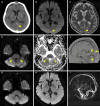

Cerebral venous thrombosis (CVT) is challenging to diagnose, as it presents with variable symptoms. We encountered a complicated case of CVT that mimicked limbic encephalitis due to sensory aphasia. Based on the characteristic magnetic resonance imaging findings, this 72-year-old Japanese man was later confirmed to have CVT, the cause of which was periodontitis due to Eikenella corrodens, a Gram-negative facultative anaerobic that is part of the mouth's normal flora. The symptoms improved without sequelae following anticoagulation treatment and antibiotics. Clinicians should consider CVT as a differential diagnosis when unexplainable neurological symptoms suggesting limbic encephalitis are observed.